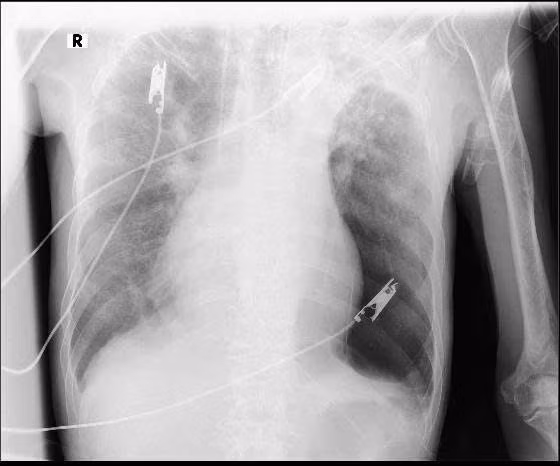

Kết quả chẩn đoán hình ảnh cho thấy tổn thương phổi hai bên rất nặng, kèm theo tràn dịch màng phổi bên phải và tràn khí màng phổi bên trái. Xét nghiệm đờm phát hiện trực khuẩn kháng cồn – kháng toan, gợi ý lao phổi đang hoạt động trên nền phổi đã bị phá hủy kéo dài.

hut-thuoc4.jpg

Phổi của bệnh nhân trên phim chụp - Ảnh BVCC

Theo ThS.BS Trương Tư Thế Bảo, đây là hậu quả điển hình của lao phổi không được điều trị triệt để, kết hợp với việc hút thuốc lá và lạm dụng rượu bia trong nhiều năm, khiến cấu trúc phổi bị tổn thương lan tỏa, khả năng trao đổi khí suy giảm nghiêm trọng và rất khó hồi phục.